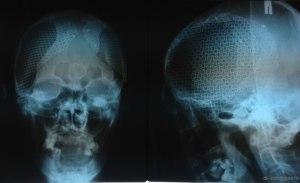

Сколько раз могут делать трепанацию черепа?

1. Трепанация черепа - это хирургическая процедура, при которой производится отверстие в черепной коробке для доступа к мозгу.

2. Обычно трепанацию черепа делают в медицинских целях, таких как удаление опухоли, снятие внутричерепного давления или облегчение симптомов травмы мозга.